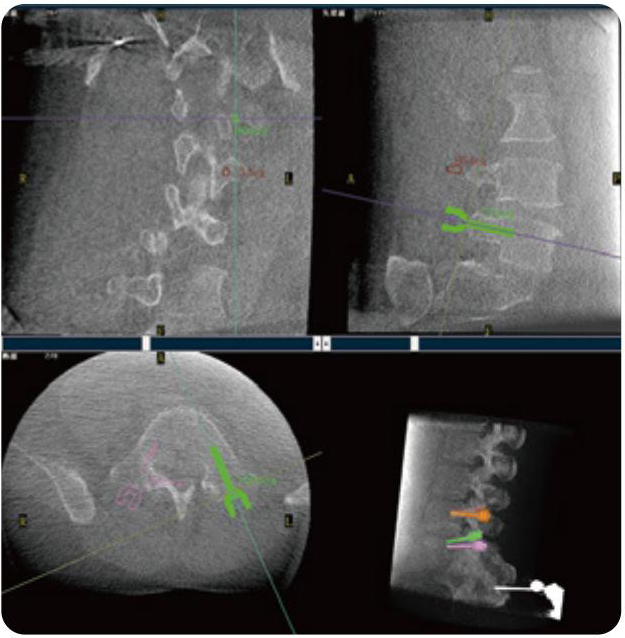

PL300B可應(yīng)用于多節(jié)段脊柱外科手術(shù),輔助醫(yī)生定位病灶部位,為脊柱外科手術(shù)(經(jīng)皮椎體成形術(shù)、椎弓根螺釘內(nèi)固定術(shù)等術(shù)式)提供術(shù)前手術(shù)流程規(guī)劃、入釘位置、角度可視化引導(dǎo),模擬仿真入釘輔助。

PL300B搭配普愛醫(yī)療自主研發(fā)生產(chǎn)的平板3D C形臂,借助一體化自適應(yīng)配準(zhǔn)( 軌跡配準(zhǔn))技術(shù),通過(guò)追蹤C(jī)形臂三維采集軌跡,自動(dòng)完成圖像坐標(biāo)建立和系統(tǒng)坐標(biāo)配準(zhǔn)。配準(zhǔn)精度更高,操作步驟少,系統(tǒng)運(yùn)作效率高。